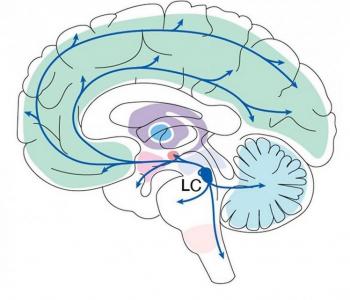

Ces scientifiques et neurologues du MIT Picower Institute jettent une nouvelle lumière sur une petite zone du cerveau, encore peu connue mais clairement spécialisée, le locus coeruleus (LC). Ces travaux, soutenus par les National Institutes of Health (NIH), révèlent que le LC n'a pas seulement un rôle d'alarme, tel que déjà documenté, mais a un impact plus nuancé et multiforme sur l'apprentissage, le comportement et la santé mentale. « D’ailleurs », le locus coeruleus est localisé profondément mais projette des circuits dans le cerveau "tout entier".

Le locus coeruleus est mieux connu pour sa production « démesurée » de norépinéphrine, un neuromodulateur stimulant l'excitation. Recevant des signaux de plus de 100 autres régions du cerveau et exerçant un contrôle du site et du moment où il « expédie » la noradrénaline (NE) qu’il produit, le LC comprend une population de cellules étonnamment diverses. Ces cellules semblent réguler l'apprentissage de la récompense et de la punition et permettre l’exploitation de ces expériences pour optimiser le comportement. L’auteur principal, le Dr Mriganka Sur, professeur de neurosciences à l'Institut Picower ajoute sur le LC : « ce qui était jusque-là considéré comme un noyau homogène exerçant une influence globale et uniforme sur ses nombreuses régions cérébrales cibles pourrait en fait être une population hétérogène de cellules libérant la noradrénaline de manière à apprendre de l’expérience.